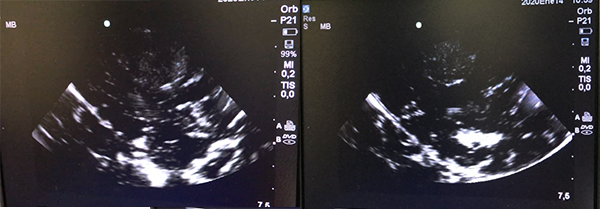

Se realiza craneotomía por un abordaje parietal izquierdo, tras durotomía sin evidencia de expresión cortical de la lesión, por lo que se empleó ecografía intraoperatoria (figura 3) localizando la lesión en área sensitiva primaria; se realizó disección roma a través del surco post central, ubicando la lesión a 5 mm de corteza; finalmente se procedió a exéresis macroscópicamente completa de ésta (figura 4).

Figura 3: (A,B) Ecografía intra-operatoria transcortical. En el plano coronal se visualiza lesión intra-axial hiperecogénica heterogénea que se diferencia de la ecotextura normal más hipogénica del cerebro normal que lo rodea, además del refuerzo periférico concordante con calcificación visualizada en TC previa.